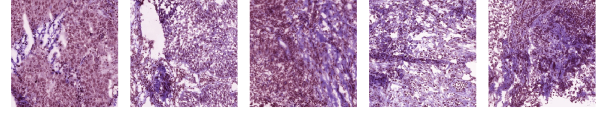

| Cluster 49 ( |

| Cluster 48 () |

![]() |

| Cluster 11 ( |